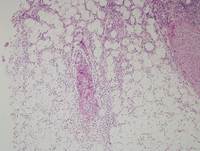

Category: Lymphoma: Mature T and NK cell lymphoproliferations > EBV+ T- and NK-cell lymphoproliferations > Chronic Active EBV Infection > Cutaneous Chronic Active EBV Infection > Hydroa Vacciniforme-like Lymphoproliferative Disorder